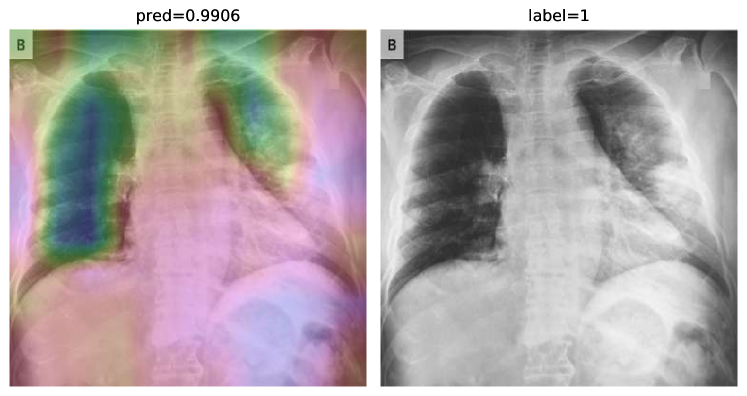

Regarding CheXNet pretrained model, we first probe to see if it is capable of correctly classifying COVID-19 pneumonia with no further improvements. Fig. 14 shows results for two sample CXRs from both classes.

Refer to caption

(a)

(b)

Figure 14: CheXNet probabilities of different classes for (a) a COVID-19 positive case, and (b) a normal case

Extracted heatmaps reveal that CheXNet correctly marks chest lobes to determine each class probability. The output of each class is slightly higher in positive cases for most of the diseases as well. Some of the drawbacks are extremely high predictions for infiltration in most of the dataset images, getting stuck in regions outside lung boundaries and predominantly in corners, and missing some of the opacities particularly in lower lobes.